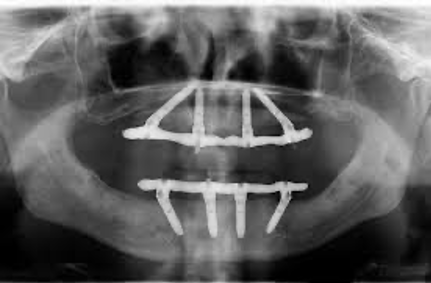

The “all-on-four” treatment concept was developed to maximize the use of available remnant bone in atrophic jaws, allowing immediate function. The protocol uses four implants in the anterior part of complete edentulous jaws to support a provisional/ fixed prosthesis.